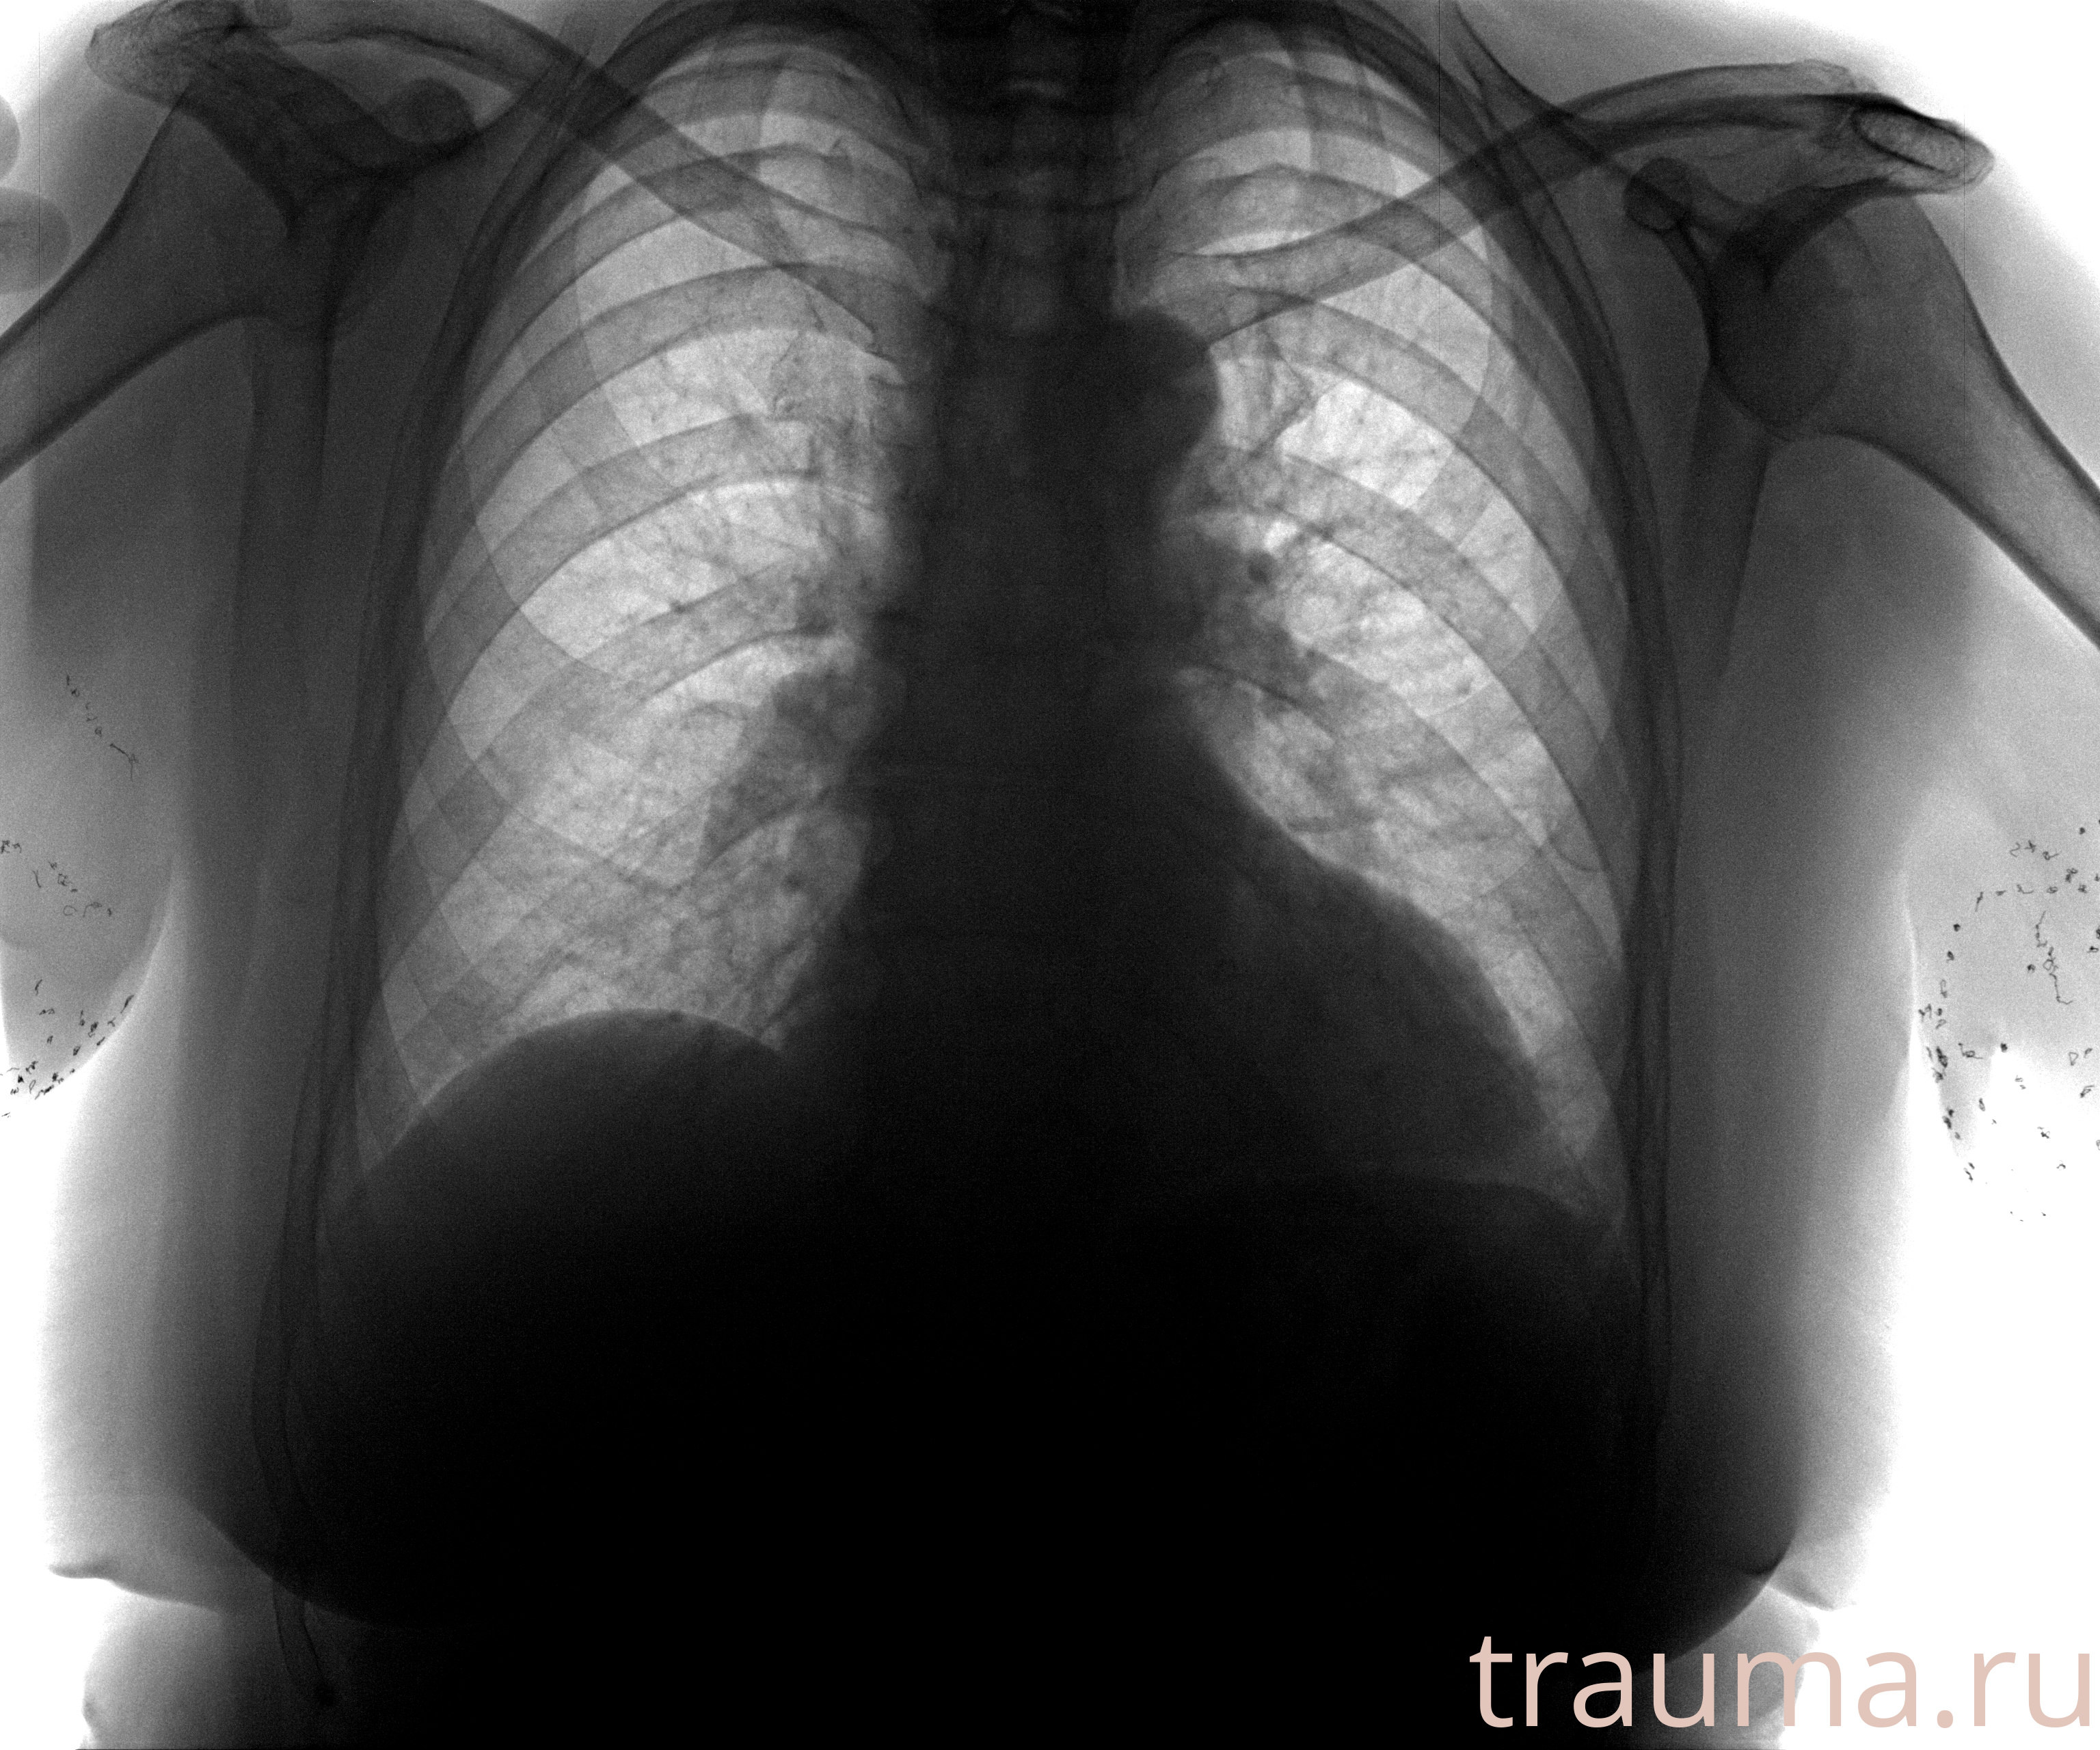

Рентген на дому: по вашему адресу приезжает врач-рентгенолог, травматолог-ортопед с мобильным рентгеновским аппаратом, проводит диагностику травмы или заболевания, делает необходимые рентгенограммы, дает рекомендации по дальнейшему лечению. Получить качественные снимки в домашних условиях возможно благодаря уникальной методике, разработанной МосРентген Центром для института  Склифосовского

при переломе шейки бедра и пневмонии от компании МосРентген Центр - партнера Института имени Склифосовского